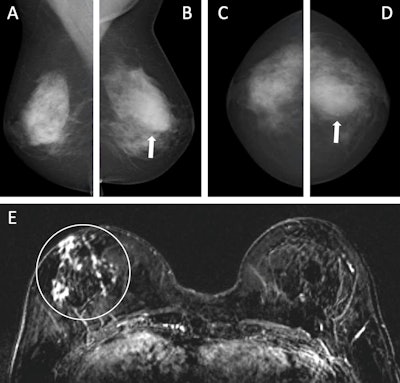

Images depict a 55-year-old woman with a family history of breast cancer who underwent combined mammography and MRI screening. (A) Right and (B) left mediolateral oblique and (C) right and (D) left craniocaudal mammograms show a large known cyst in the left breast (arrow in B and D), but were otherwise assessed as being unremarkable. Breast tissue was judged to be extremely dense. (E) Concurrent axial subtraction MRI scan shows a large, diffuse, invasive lobular cancer (circle) in the right breast. The AI system provided a case-based cancer suspicion score of 8 on a scale of 0-10, which would have led to selection for MRI screening using both the score 5 and score 8 thresholds, but not the score 9 threshold.Images depict a 55-year-old woman with a family history of breast cancer who underwent combined mammography and MRI screening. (A) Right and (B) left mediolateral oblique and (C) right and (D) left craniocaudal mammograms show a large known cyst in the left breast (arrow in B and D), but were otherwise assessed as being unremarkable. Breast tissue was judged to be extremely dense. (E) Concurrent axial subtraction MRI scan shows a large, diffuse, invasive lobular cancer (circle) in the right breast. The AI system provided a case-based cancer suspicion score of 8 on a scale of 0-10, which would have led to selection for MRI screening using both the score 5 and score 8 thresholds, but not the score 9 threshold.RSNA